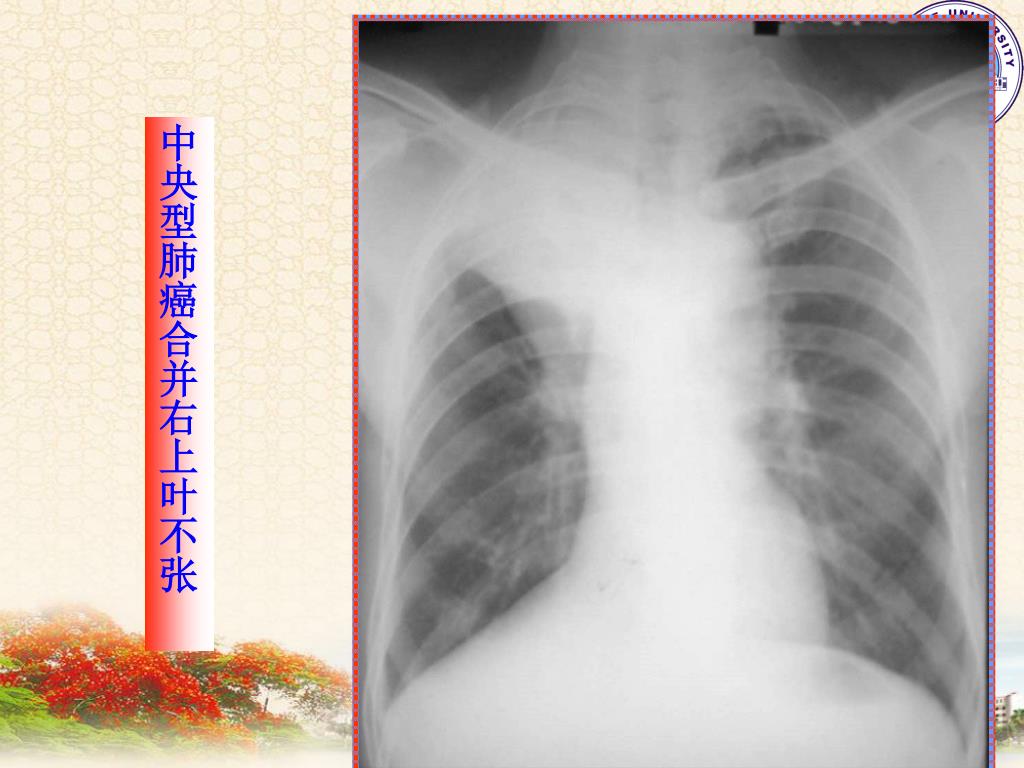

13. 中央型肺癌合并右上叶不张

14. 中央型肺癌合并右上叶不张

9. 【影像学表现】 1、阴性表现:病灶小。 2、间接征象: ①阻塞性肺气肿 深呼气易于显示。 ②阻塞性肺炎 分泌物引流不畅, ③阻塞性肺不张 支气管完全阻塞则出 现癌瘤向支气管外蔓延,形成肺门区肿 块。右上叶肺癌可出现典型的横“S”征。

10. ④支气管扩张 支气管扩张呈带状 及条状致密影称为“手套征”。 3、直接征象:癌瘤向支气管管外蔓延,在 肺门区形成肿块及结节,边缘多呈分叶状 或欠规则。右侧者可示肺门角消失。 4、转移征象: 癌肿转移到邻近的肺门淋巴 结引起肺门增大、纵隔阴影增宽。